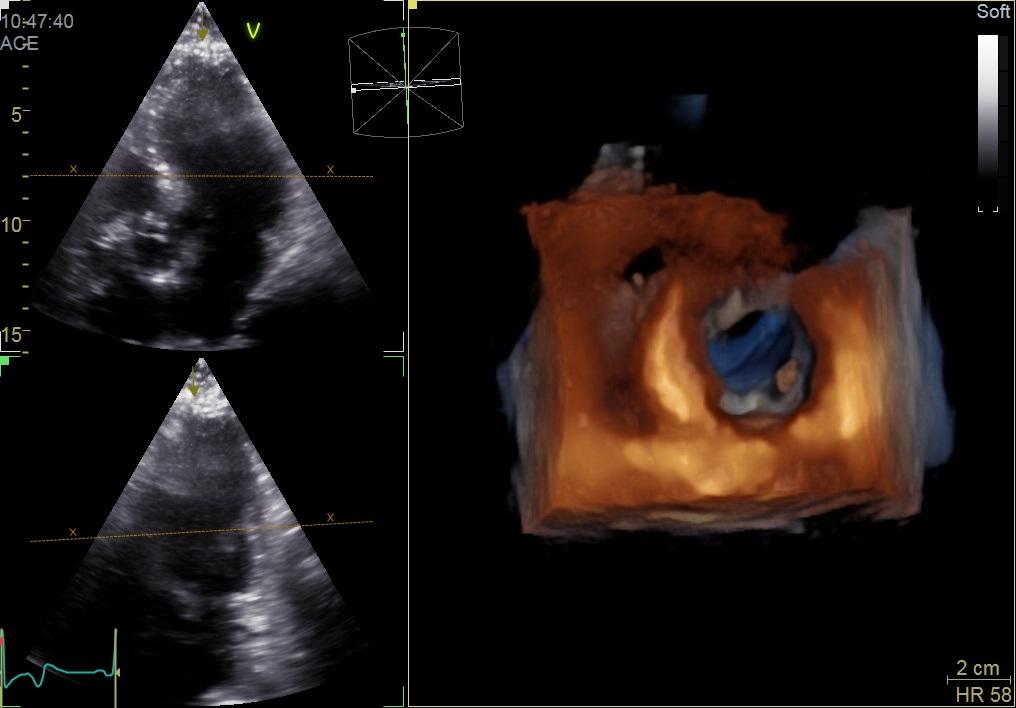

În urmă cu câțiva ani, Centrul Medical Speranța, fondat de medicul cardiolog Radu Popa, a adus în premieră în Craiova ecocardiograful 4D, un echipament de ultimă generație cu elemente de inteligență artificială pentru ecografii cardiace, standardul de aur în domeniu.

Ecocardiografia ultrarapidă 4D poate cuantifica indicii majori cardiaci Doppler într-o singură achiziție de bătăi cardiace. Acuratețea 4D este dovedită ca fiind extrem de importantă şi în ceea ce privește evaluările în Cardio-Oncologie, precizează dr. Popa.

La Clinica Speranţa, aceştia beneficiază de investigaţii cu echipamente performante. În acest an, clinica și-a extins gama de aparatură ultraperformantă și cu un echipament de ultimă generaţie pentru ecografie transesofagiană cardiacă.